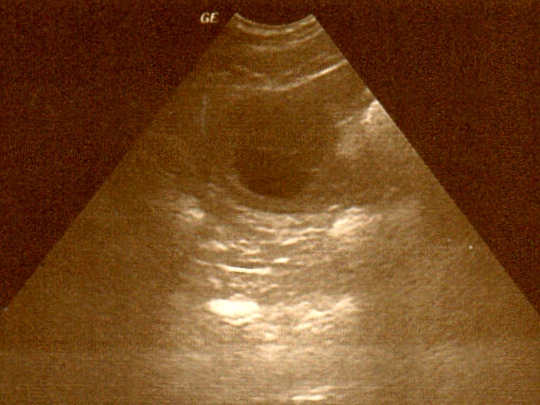

Drei Fruchtblasen waren im Ultraschall zu sehen. Es können natürlich auch mehr Welpen werden, denn meist sieht man nicht alle bei dieser Untersuchung.